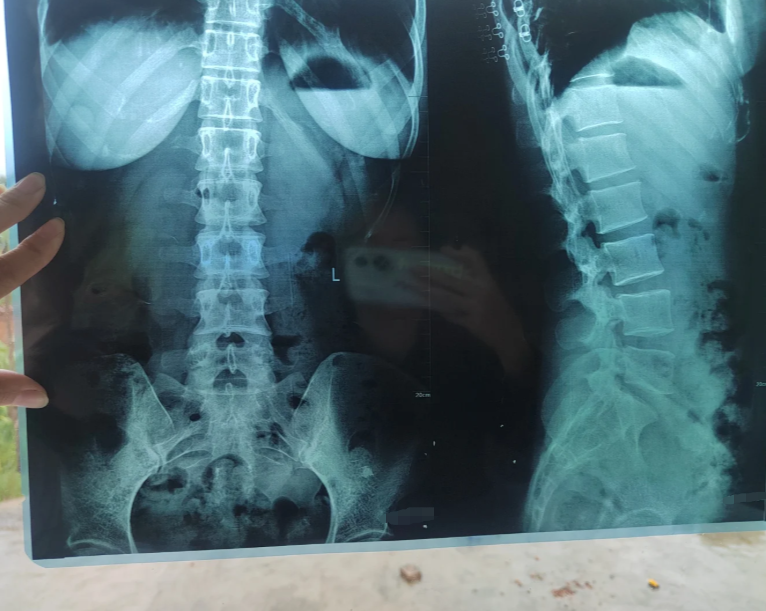

今天来看一位患外周型强直性脊柱炎2年的患者,片子上的情况如何

图片尺寸720x960